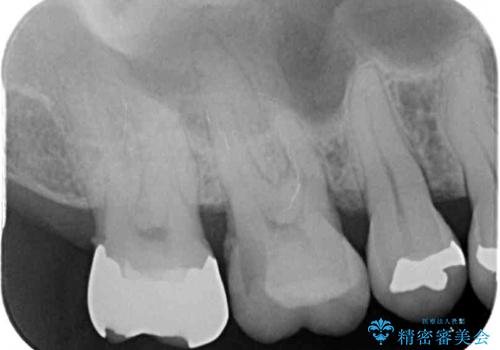

- 銀歯やインレーが外れたまま放置された奥歯の治療を希望して来院された患者様です。

咬合力が著しく強いため、欠損の多い歯はフルジルコニアクラウンへ、その他の虫歯はゴールドインレー(PGAインレー)にて修復することとしました。

来院時は全てセラミックでの治療を希望されていましたが、歯列や咬み合わせから咬合力による破損リスクが高いと判断されたため、ゴールドインレーを選択しました。